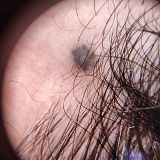

Внешне голубой невус Ядассона–Тиче представляет собой небольшого размера (до 8–10 мм в диаметре) плоскую или слегка приподнятую над кожей родинку. Поверхность такой родинки гладкая, без явной бугристости. Цвет может варьировать от голубого до тёмно-синего, причем окраска неравномерная из-за достаточно глубокого залегания образующих опухоль меланоцитов. В некоторых случаях размер невуса больше стандартного — до 3–3,5 см. Контур невуса не всегда четкий. Форма бывает круглая, вытянутая или веретенообразная. Ни равномерность окраса, ни форма родинки не является указателем на необходимость удаления или отсутствие такой потребности.

Неклеточный (простой) голубой невус выглядит как эластичный узелок, похожий на мелкое инородное тело под кожей. Диаметр темного плотного узелка обычно 6-8 мм. Цвет — от серого с голубым до насыщенного чёрного. Чаще всего вульгарный неклеточный невус обнаруживают на шее, лице, тыльной стороне ладоней и стоп. Также он может вырастать и на слизистой рта и половых органах, встречается голубой невус на губе и волосистой части головы, что может затруднять его своевременное обнаружение.